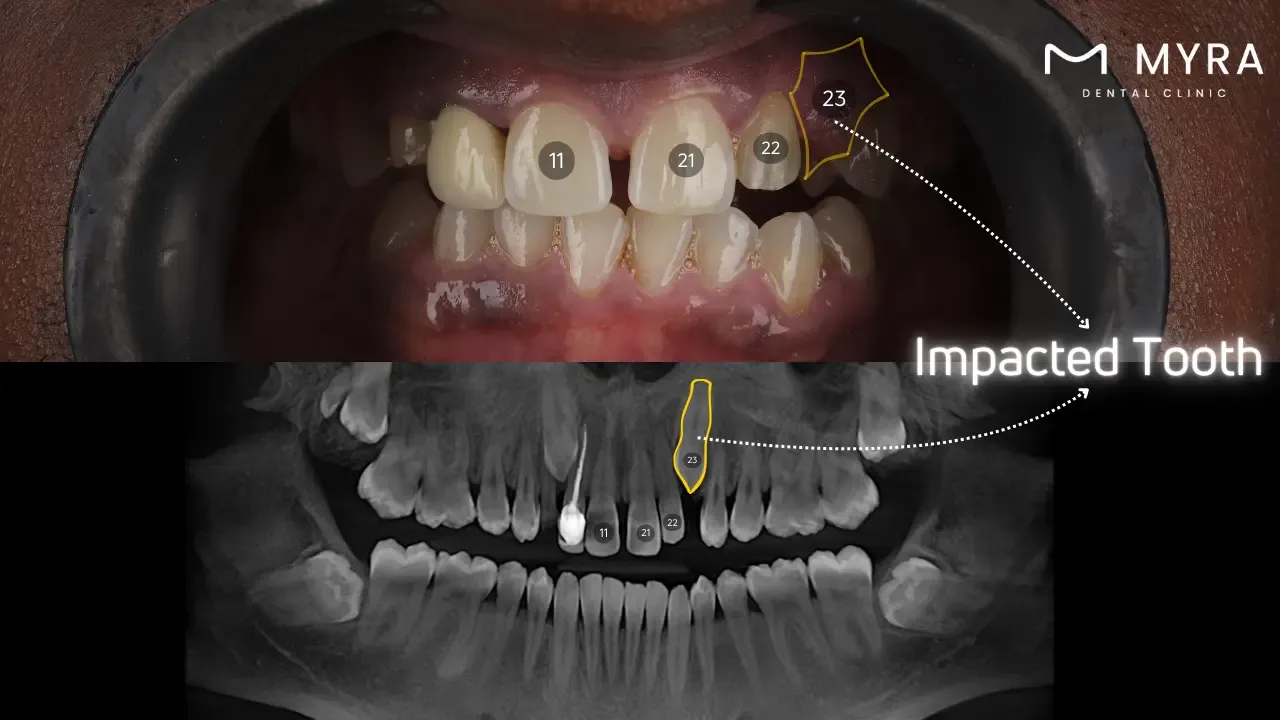

Impacted teeth are dental issues when a tooth fails to emerge correctly through the gum line. The condition is seen with wisdom teeth, the last molars to develop. Impacted teeth lead to various complications, including pain, infection, and misalignment of other teeth. Understanding the symptoms, treatment options, causes, and similar conditions and researching impacted teeth is essential for effective management and prevention.

What are the Types of Impacted Teeth?

The types of Impacted Teeth are listed below.